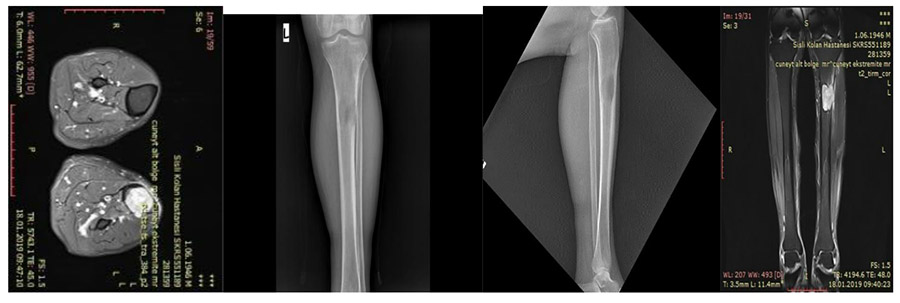

CASE 51: Lung cancer metastasis to the upper end of the left tibia increases the risk of fracture (impeding fracture).

Before the surgery: X-rays and MRIs show a metastatic focus in the upper end of the tibia, damaging the outer part of the bone and posing a risk of fracture.